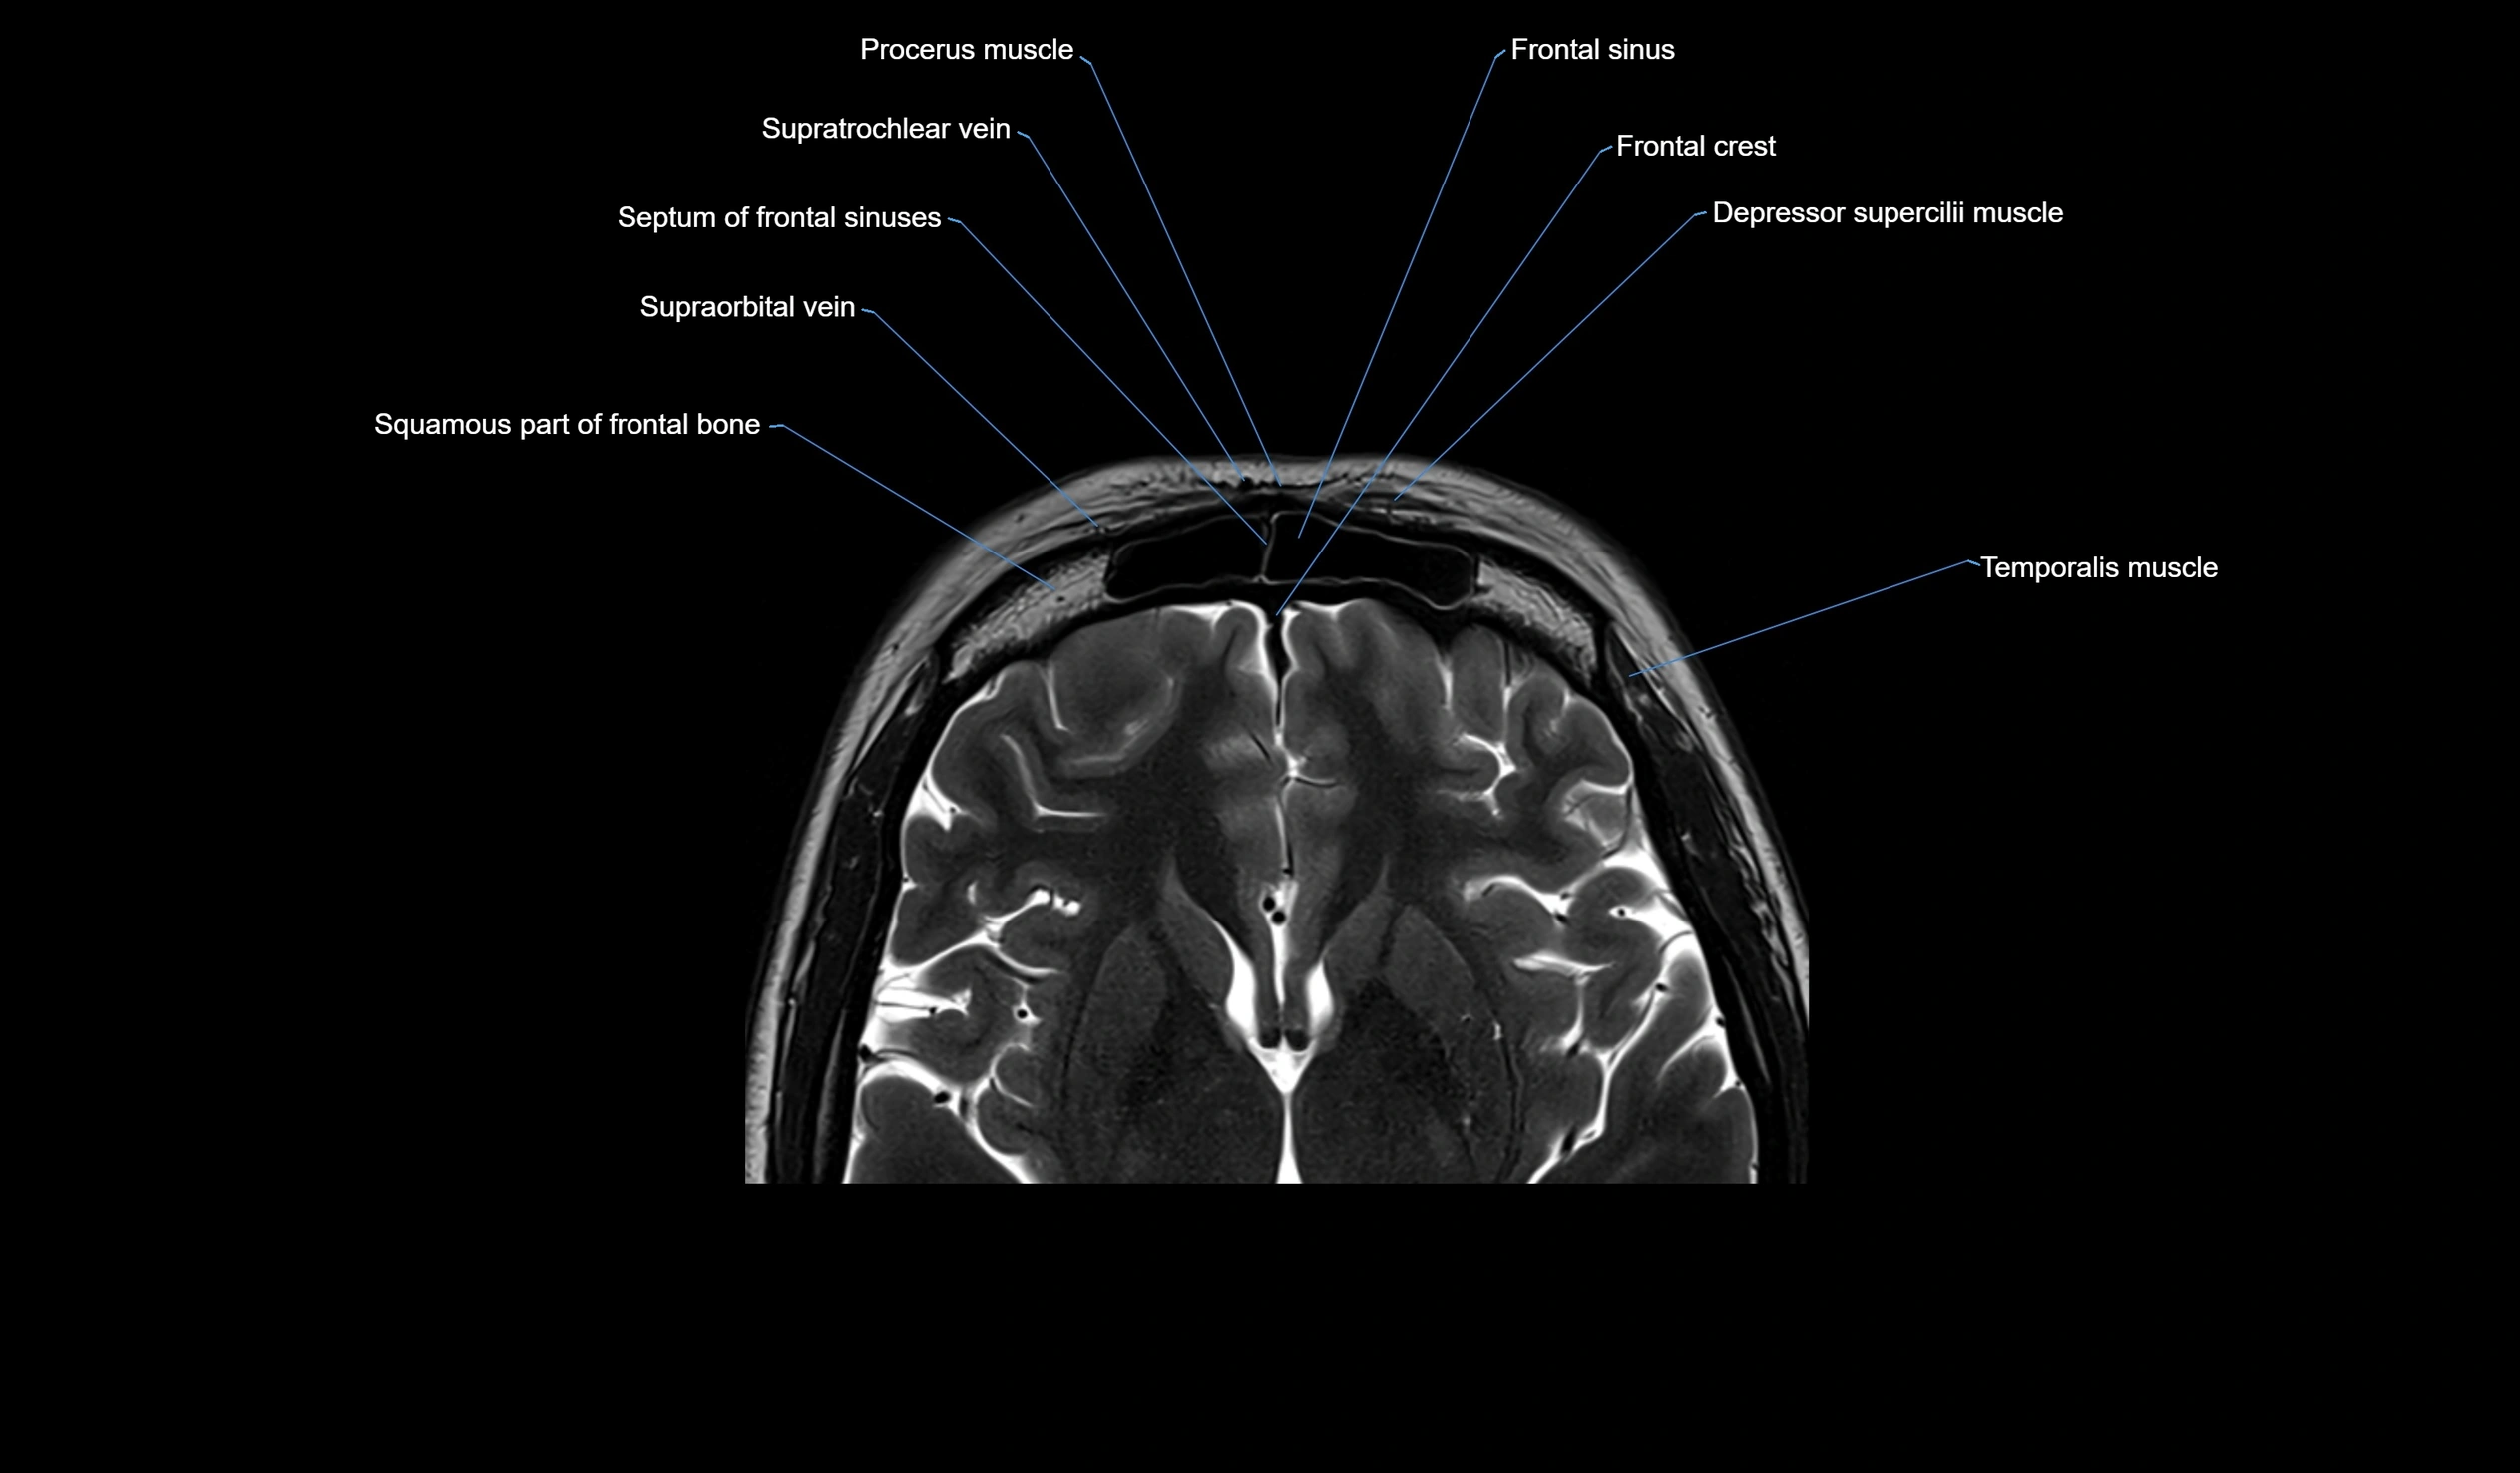

MRI images